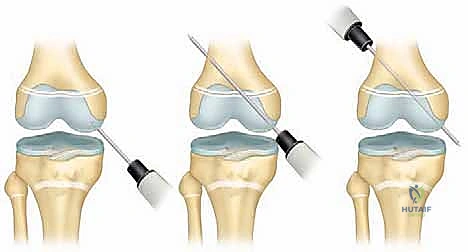

2. الرد تحت التنظير الفلوري (Fluoroscopic Reduction)

يستخدم الدكتور هطيف جهاز الأشعة السينية الحي (C-arm) لرؤية العظام في الوقت الفعلي. بفضل خبرته، يقوم بحركات ميكانيكية دقيقة ولطيفة جداً لإعادة العظام المنزاحة إلى مكانها الطبيعي (Anatomical Reduction) دون استخدام القوة المفرطة التي قد تسحق الغضروف.

3. التثبيت الداخلي (Internal Fixation)

تتطلب كسور صفيحة النمو أدوات تثبيت خاصة جداً. القاعدة الذهبية في جراحة عظام الأطفال هي: "تجنب اختراق صفيحة النمو بأدوات صلبة قدر الإمكان".

* استخدام أسلاك كيرشنر الملساء (Smooth K-wires): إذا كان لا بد من عبور صفيحة النمو لتثبيت الكسر، يستخدم الدكتور هطيف أسلاكاً معدنية ملساء تماماً (بدون تسنين)، ويتم إدخالها بزوايا متقاطعة دقيقة لضمان الثبات بأقل مساحة اختراق ممكنة، مما يسمح للصفيحة بالاستمرار في النمو.

* استخدام البراغي المجوفة (Cannulated Screws): في كسور (سالتر-هاريس النوع الثاني)، يتم إدخال البراغي عبر "شظية ثورستون-هولاند" العظمية إلى الكردوس، بشكل موازٍ لصفيحة النمو دون لمسها أو اختراقها أبداً. هذه التقنية تتطلب مهارة مكانية (Spatial awareness) عالية جداً يمتلكها الدكتور هطيف.